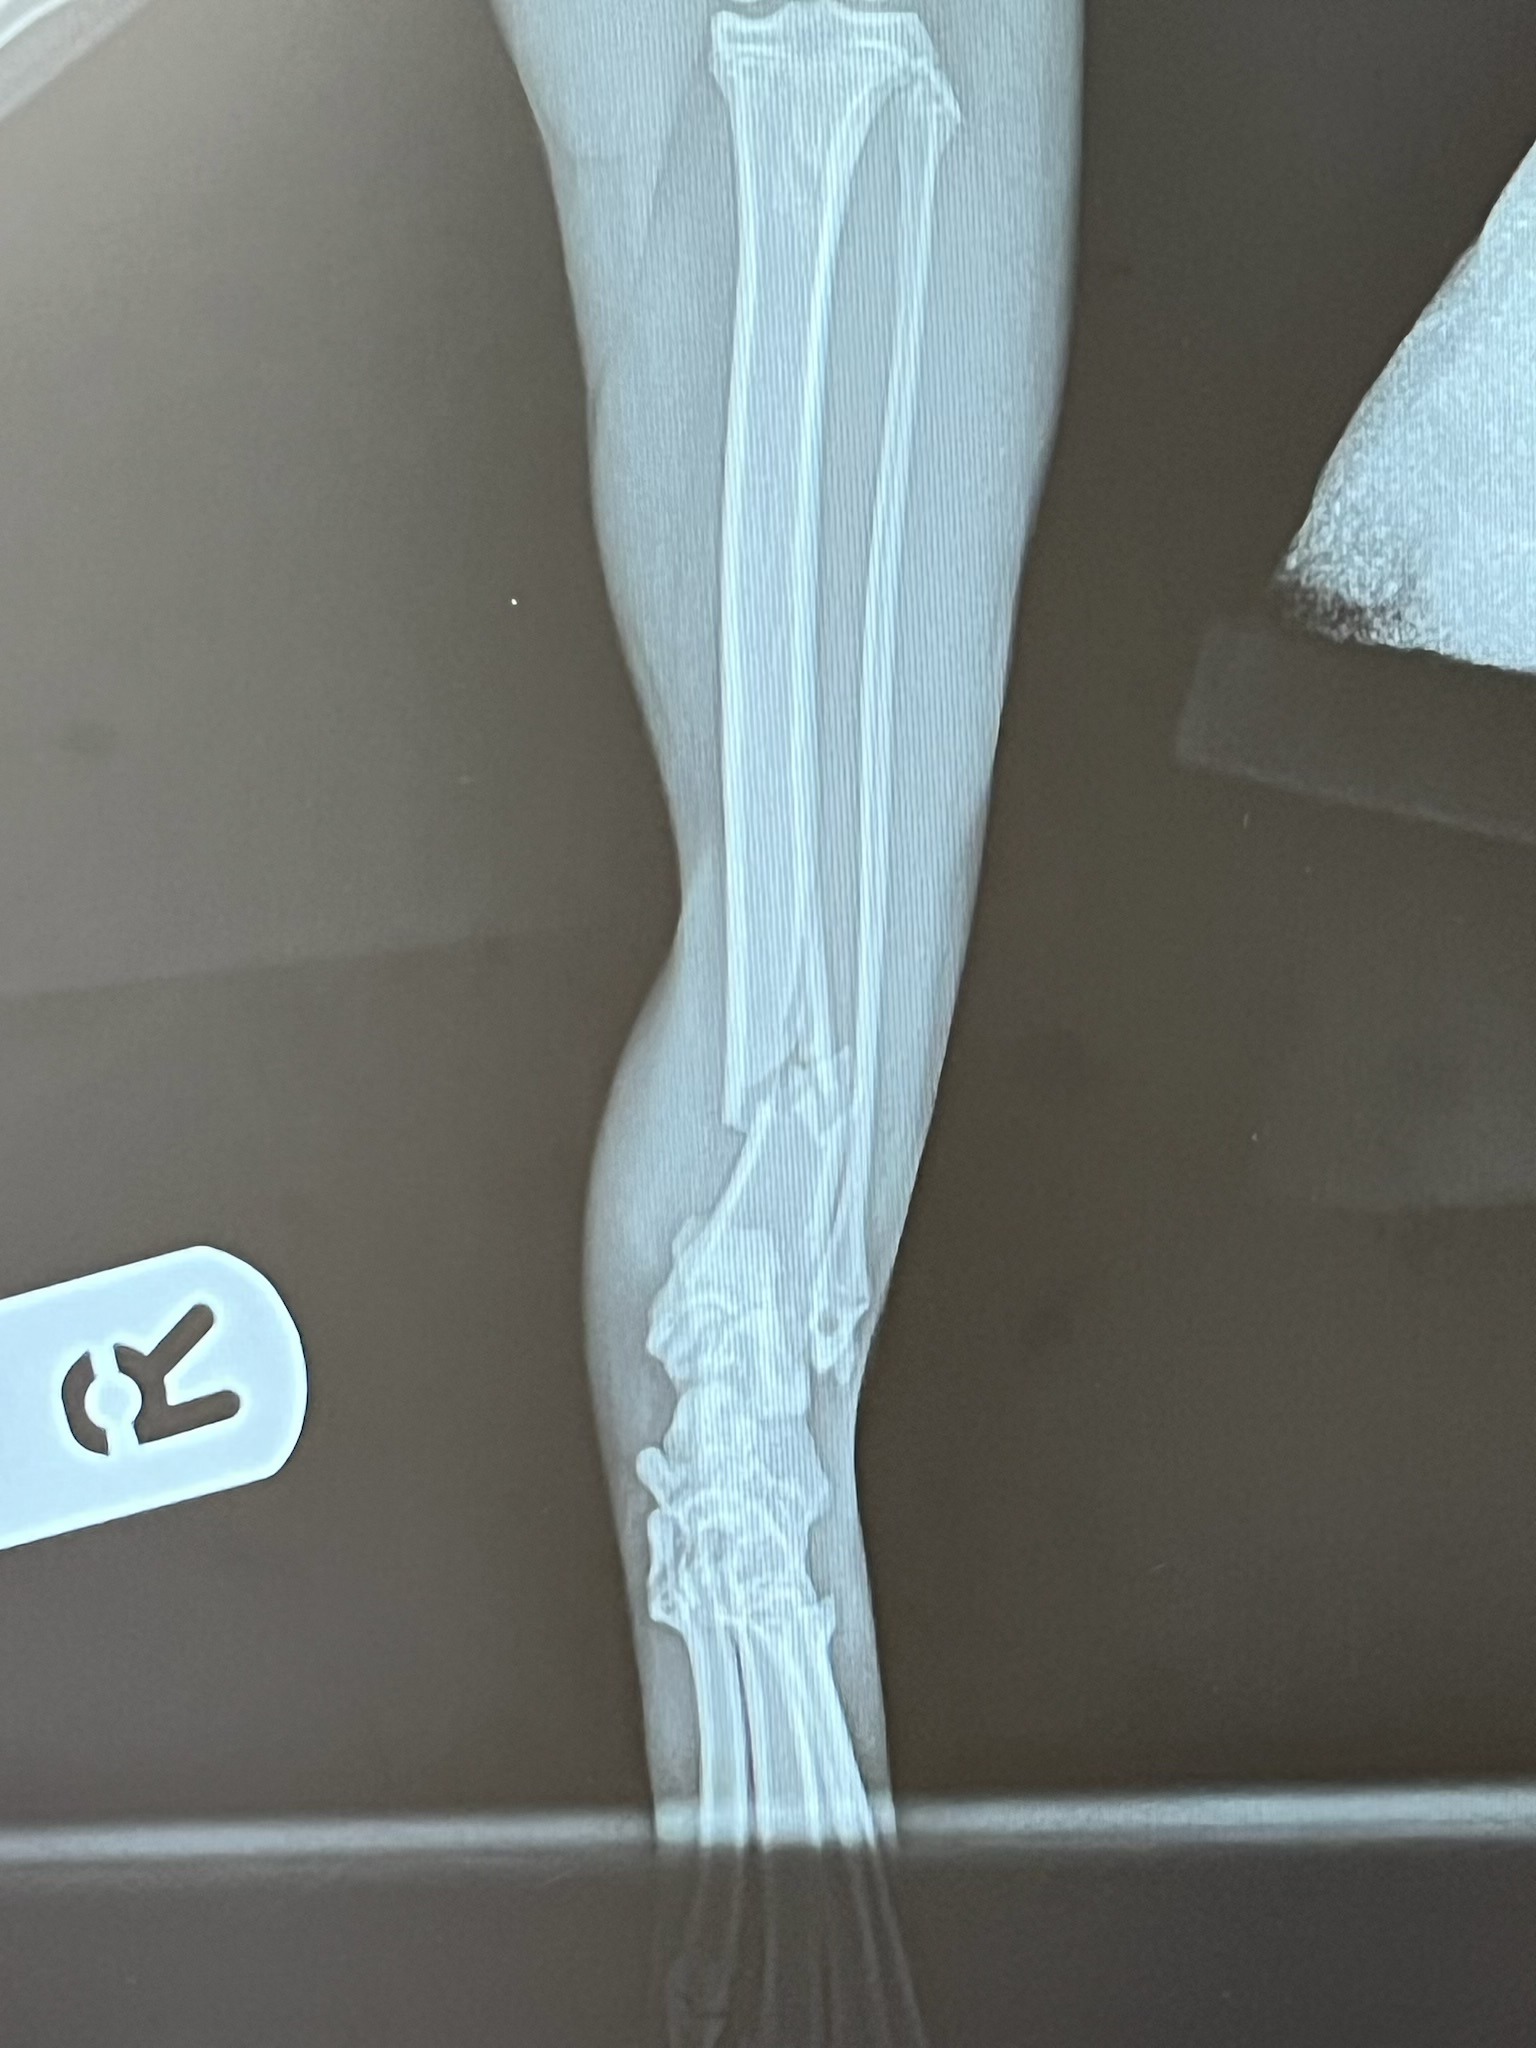

I am very upset and in pain for her as Indie has broken her hind right leg.

Having spent £300 already to have her leg x-rayed and casted, I am asking if anyone would like to help raise a bit of money so that I have enough, comfortably, going forward with the next set of vet bills I will need to pay.